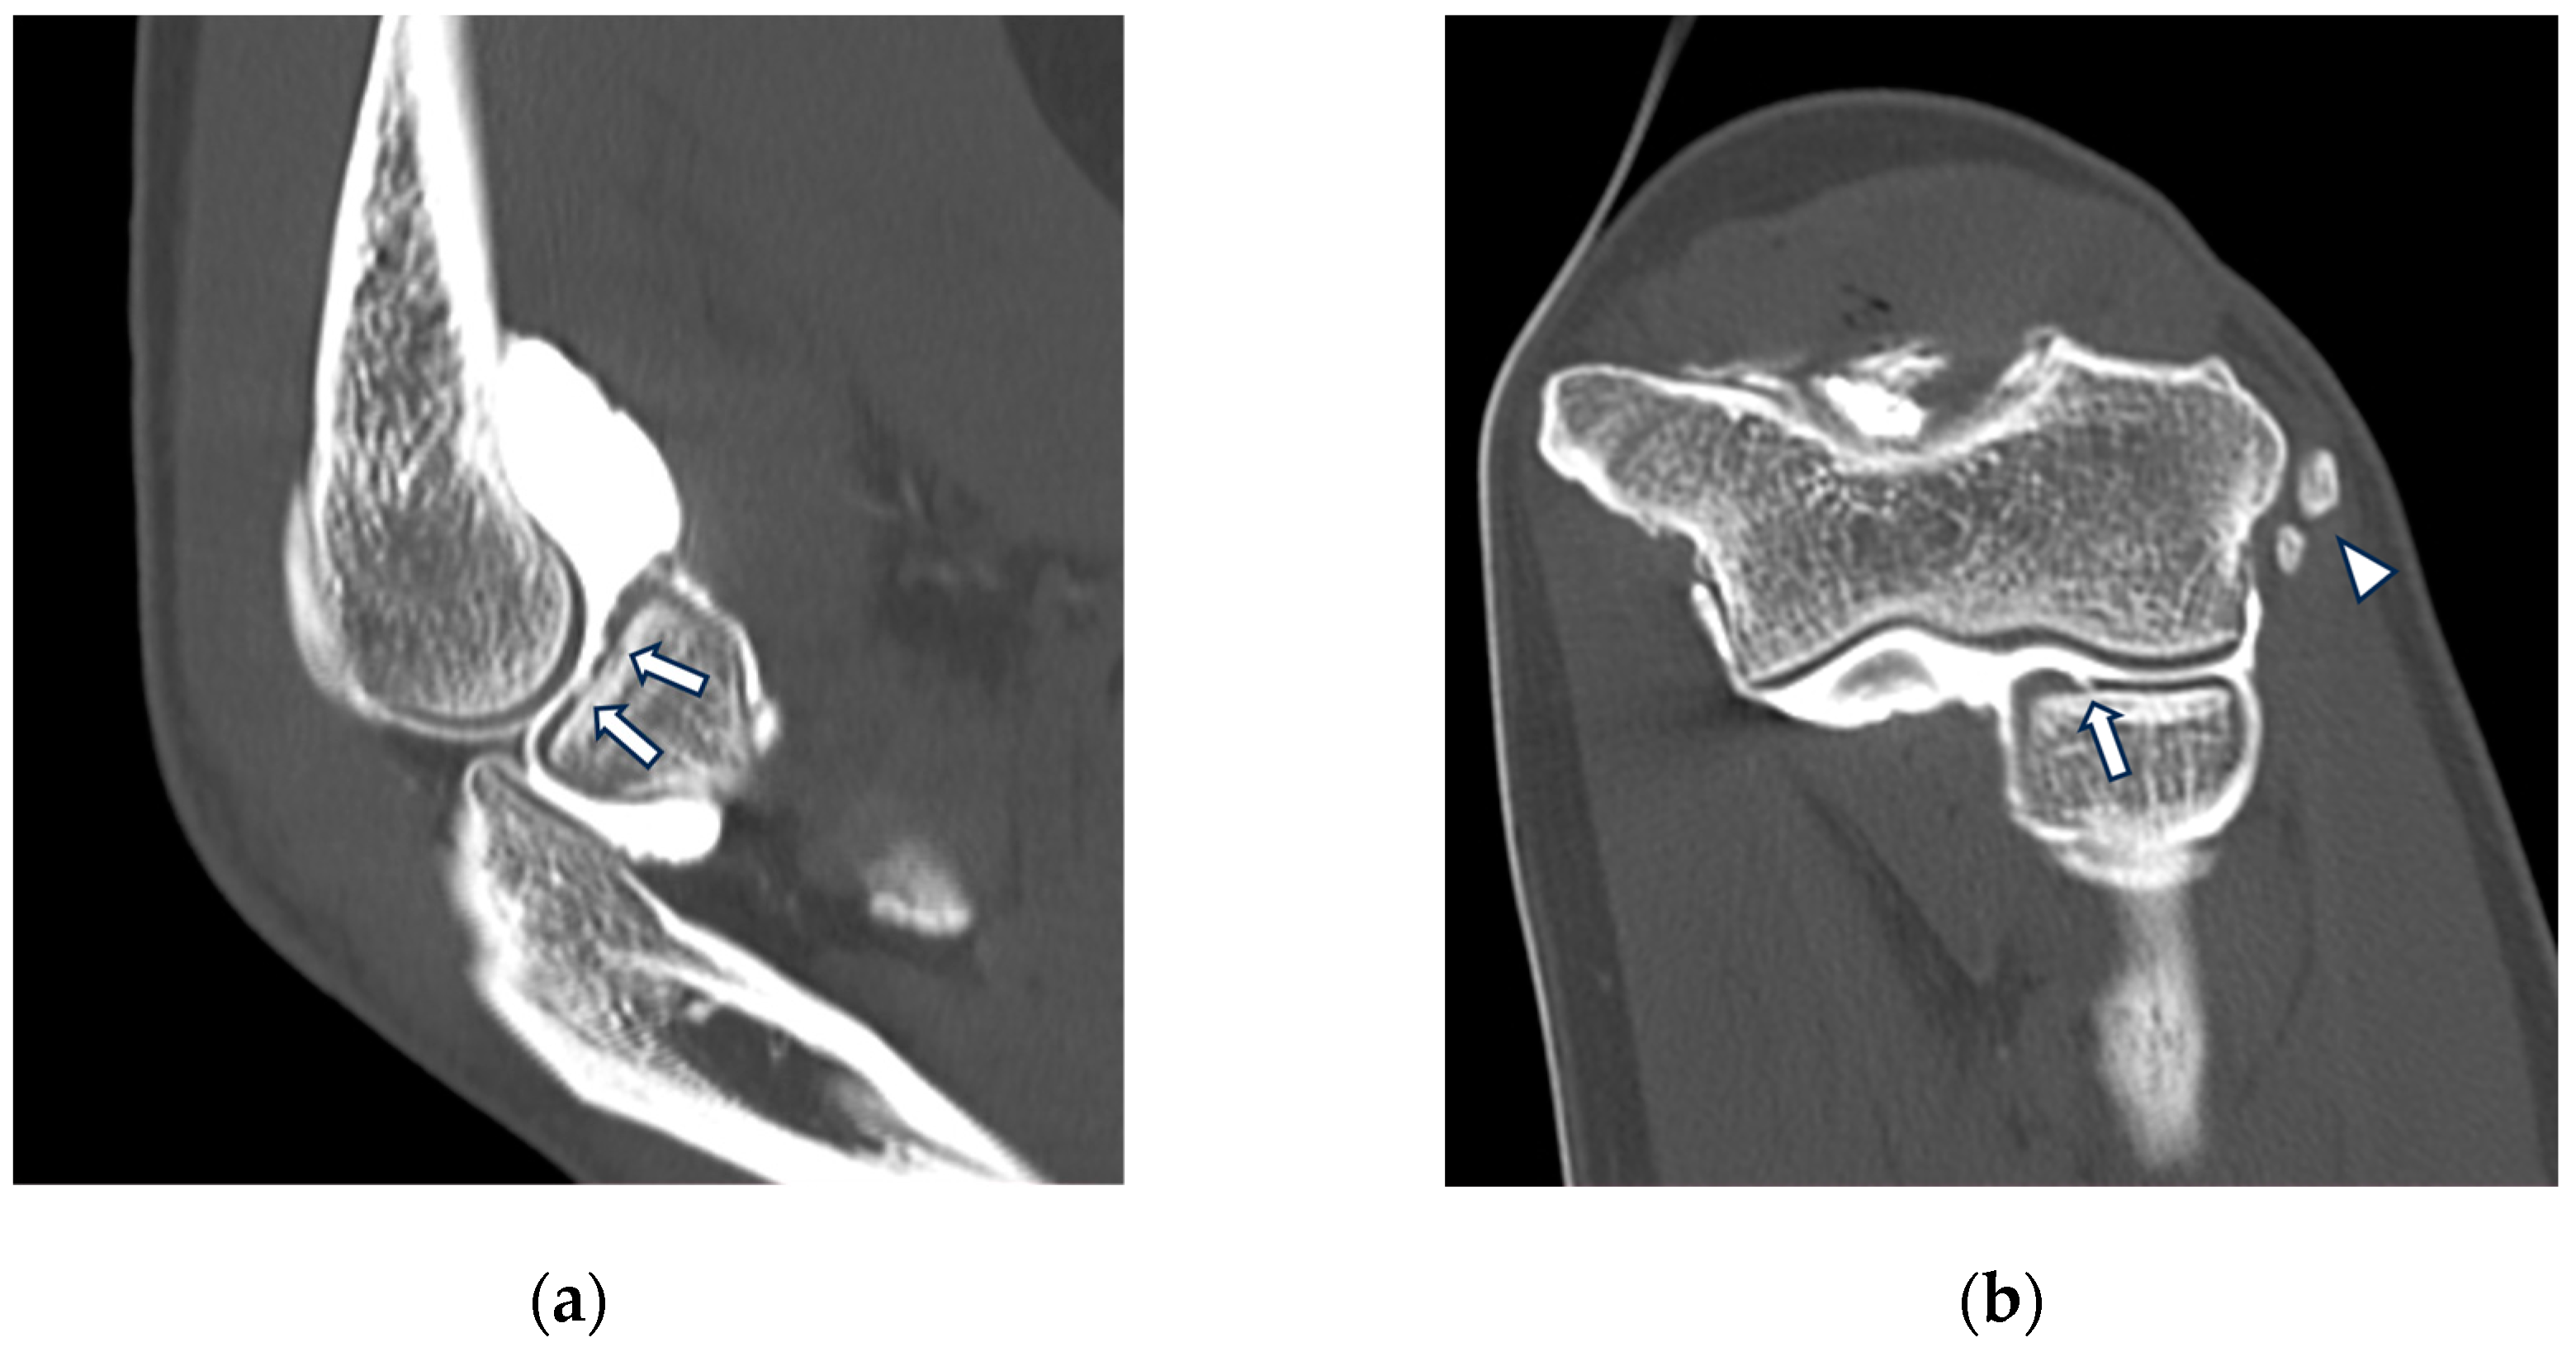

Figure 5.

CT arthrography of a patient with sequelae of traumatic elbow dislocation. (a,b) Coronal and axial images showing LCL laxity with subtle foci of contrast medium permeation due to ligament delamination (white arrowheads) and a loose body within a pathologically distended lateral recess (white arrow), as well as cartilage thinning and fraying of the lateral aspect of the capitulum humeri (yellow arrowhead). Post-traumatic deformity of the radial head can also be seen; (c) sagittal reformat shows a loose bony fragment posterior to the capitulum humeri (asterisk) and posterior synovial thickening (yellow arrow).

Figure 8.

CT arthrography of a patient with lateral epicondylitis subjected to multiple corticosteroid injections. (a,b) Coronal and axial images show extravasation of intra-articular contrast into lateral periarticular soft tissues through a large full-thickness tear of both the radial collateral ligament and the proximal common extensor tendon (white arrowheads). Diffuse thinning of radial head dish cartilage is also displayed (white arrows); (c) sagittal image also shows distal displacement of the annular ligament (yellow arrowhead) and cartilage fraying of the radial head side (yellow arrow).